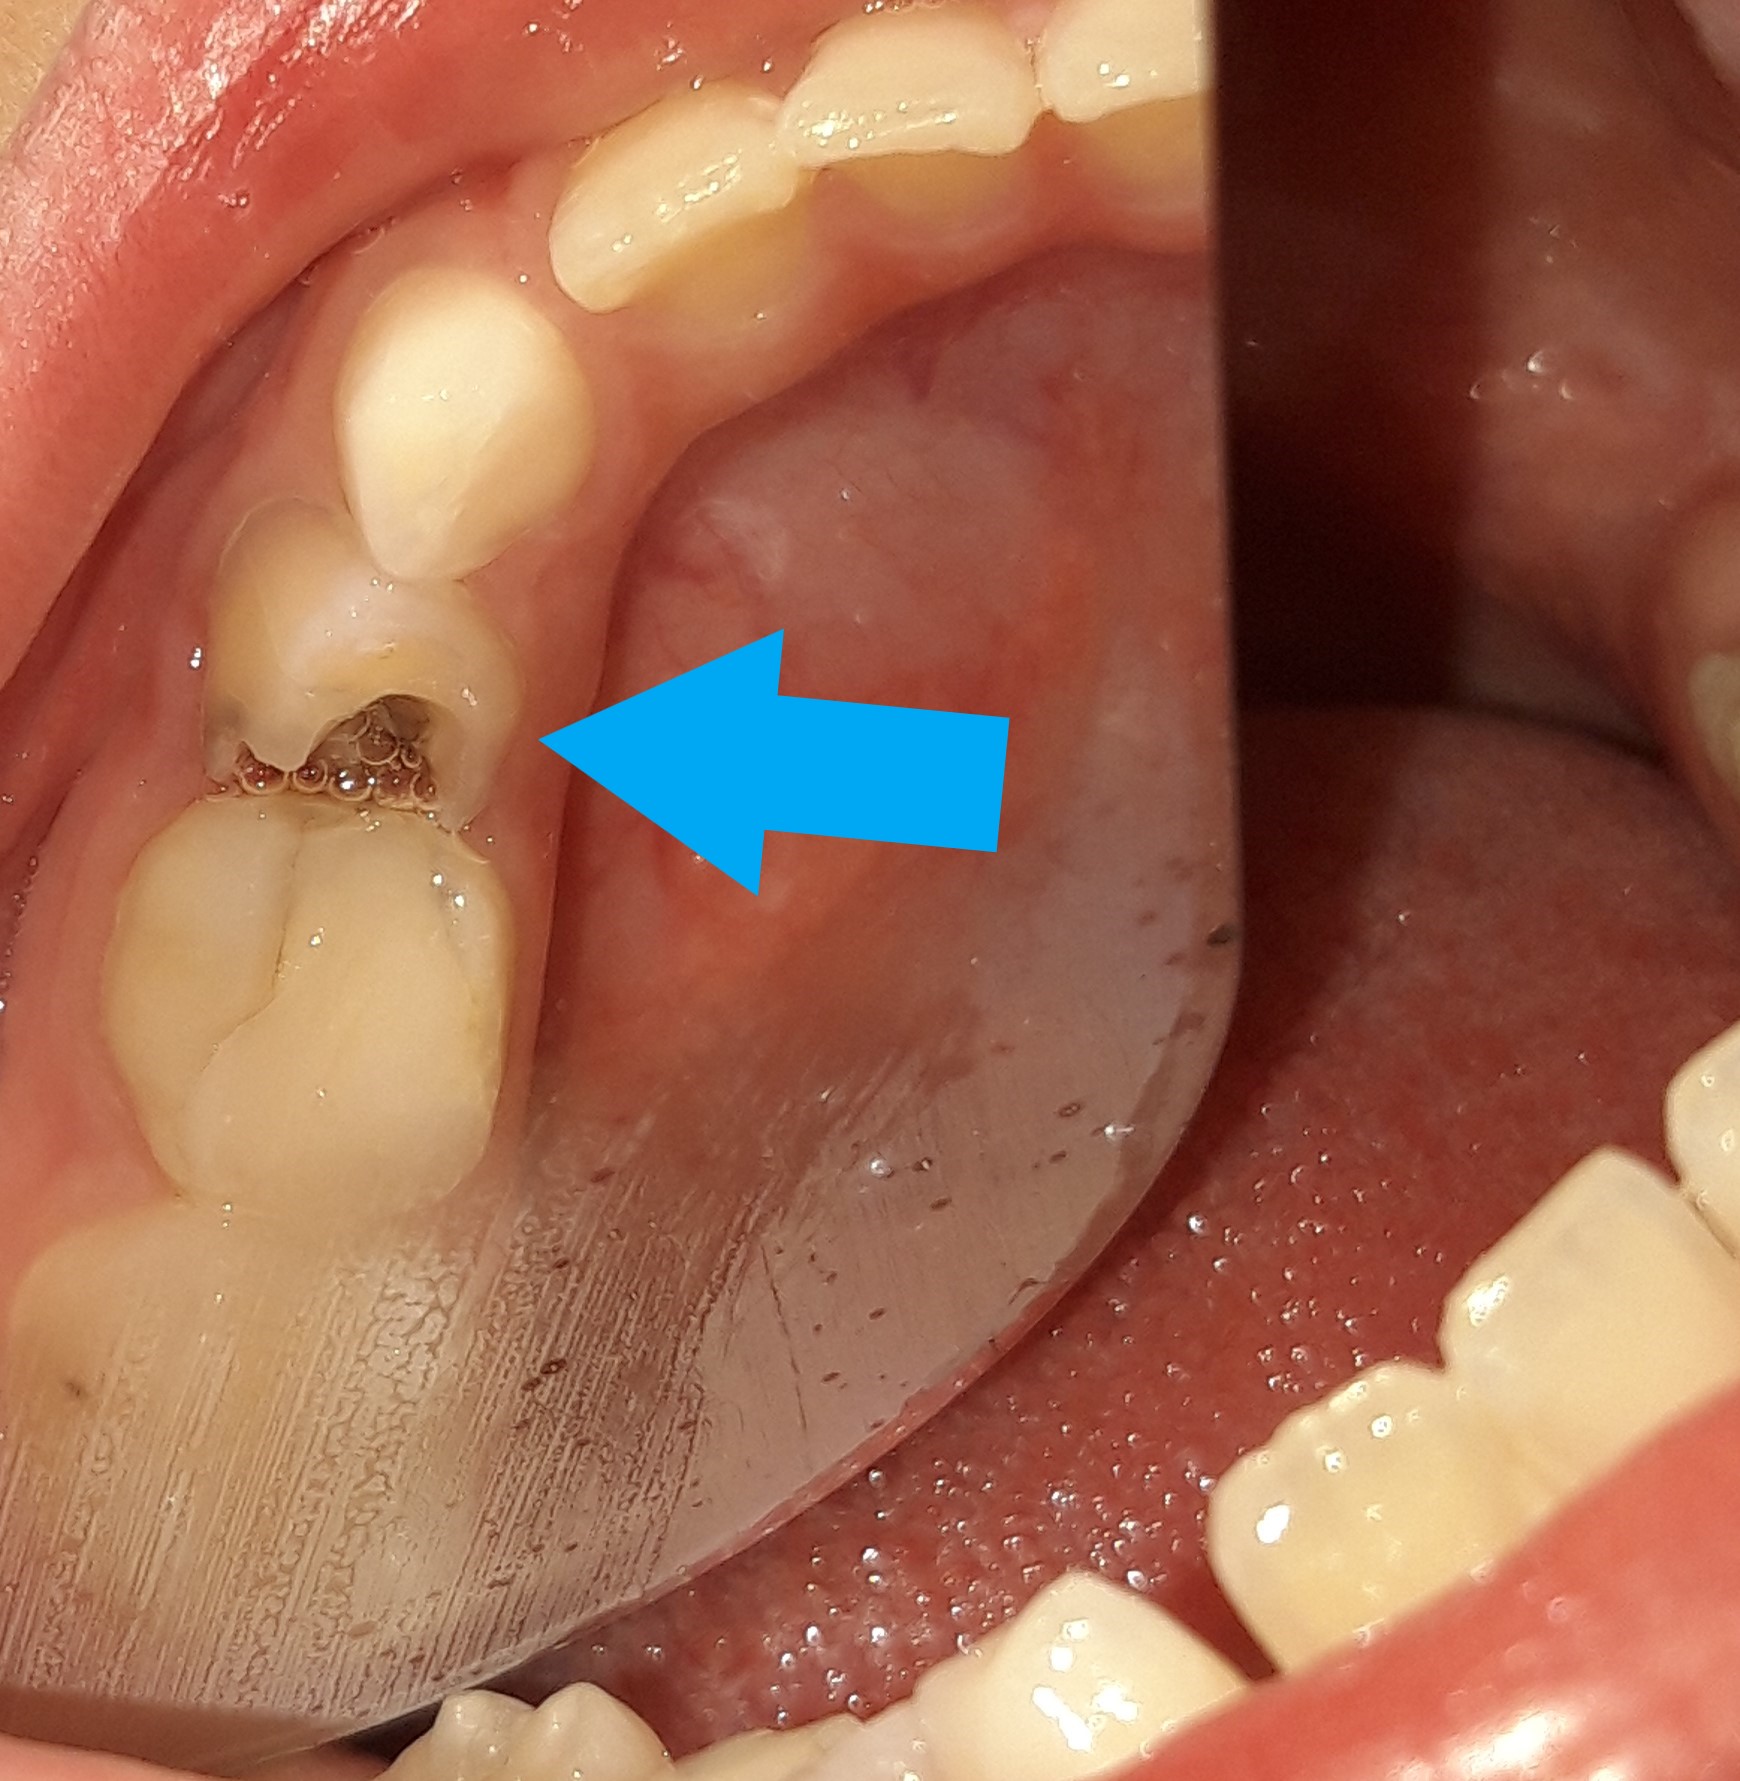

Το οδοντικό έλλειμμα στη μικρή ασθενή είναι πολύ μεγάλο και την πονά. Στο κορίτσι χορηγήθηκε τοπική αναισθησία για την εξασφάλιση μιας ανώδυνης οδοντιατρικής θεραπείας. Το δόντι δεν πονά πλέον την μικρή ασθενή, η οποία μπορεί άφοβα να τρώει από την κάτω δεξιά πλευρά χωρίς παράπονα.

ΠΡΙΝ

ΜΕΤΑ